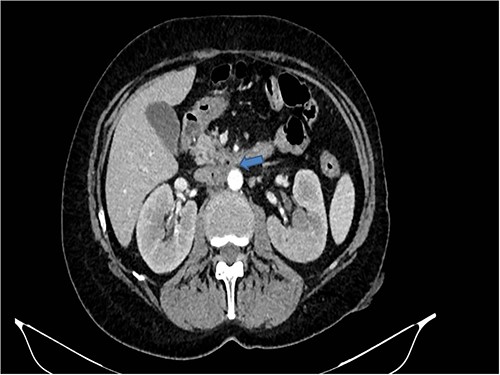

A 58-years-old woman arrived to our emergency department for fever (39.5°C) with chills and diffuse abdominal pain radiating to the back about 2 weeks. Her medical history included a hysteroannexectomy with sigmoid resection for an ovarian tumor that occurred 2 years earlier (Stage IIb) and adjuvant radiotherapy and traditional chemotherapy, subsequently followed by biological therapy with bevacizumab completed 6 months earlier. The patient was currently disease free and in follow-up. On admission, laboratory test showed a white cell count of 18 700 mL and microcytic anemia (hemoglobin level, 6.6 g/dL) with an increase in inflammation indices (CRP 26.2 mg/dl). Evidence of several digestive tract bacteria, including Enterococcus faecium, Escherichia coli and Weissella confusa, was disclosed by means of several hemocultures. A specific antibiotic therapy was started and blood transfusions were performed for the anemia found. Therefore, the patient underwent a chest and abdomen CT scan, which showed the presence of strong adherence between the IVC at the origin of the left renal vein and the third duodenal portion with air inside the vena cava and thrombotic-like hypodense material as for a DCF (Figs 1 and 2).

CT scan showed the presence of strong adherence between the IVC at the origin of the left renal vein and the third duodenal portion.